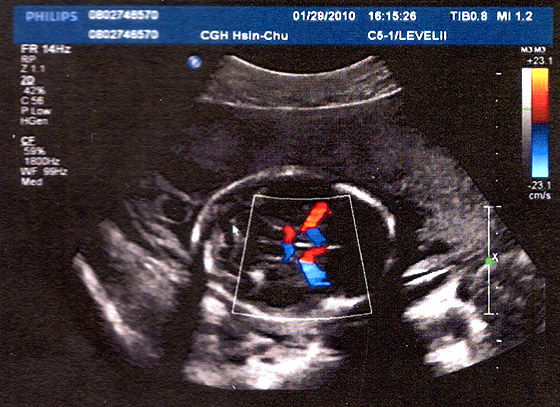

又是一張不知所云的超音波照片…

不過這次是彩色版啦 (有顏色的部份表示血液流動的方向)

這個. 好像是大腦 (?)

根據醫生的說法. 兩邊長得有對襯到. 很好!